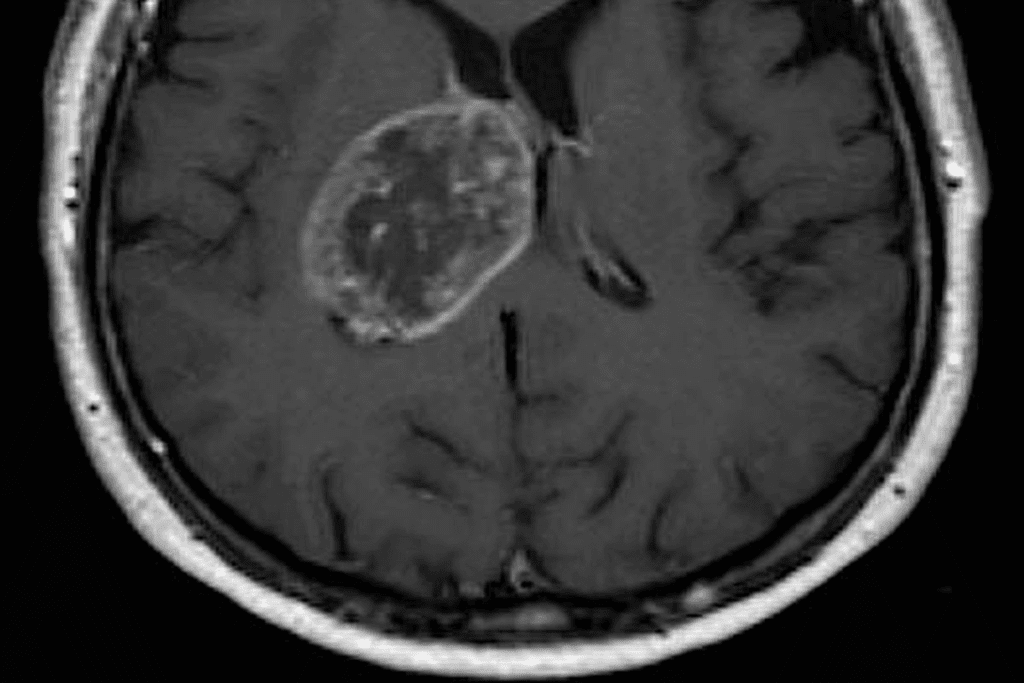

Imaging Tests

Imaging tests are very important for diagnosing brain tumors in kids. The main tests are:

- Magnetic Resonance Imaging (MRI)

- Computed Tomography (CT) scans

- Positron Emission Tomography (PET) scans

These tests help doctors see the tumor, its size, and where it is. They also check how it affects the brain around it.